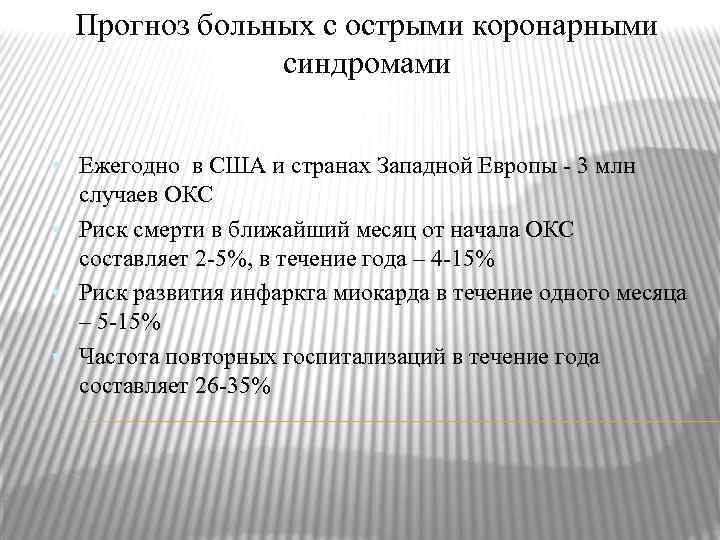

Прогноз больных с острыми коронарными синдромами • Ежегодно в США и странах Западной Европы - 3 млн случаев ОКС • Риск смерти в ближайший месяц от начала ОКС составляет 2 -5%, в течение года – 4 -15% • Риск развития инфаркта миокарда в течение одного месяца – 5 -15% • Частота повторных госпитализаций в течение года составляет 26 -35%

Прогноз больных с острыми коронарными синдромами • Ежегодно в США и странах Западной Европы - 3 млн случаев ОКС • Риск смерти в ближайший месяц от начала ОКС составляет 2 -5%, в течение года – 4 -15% • Риск развития инфаркта миокарда в течение одного месяца – 5 -15% • Частота повторных госпитализаций в течение года составляет 26 -35%